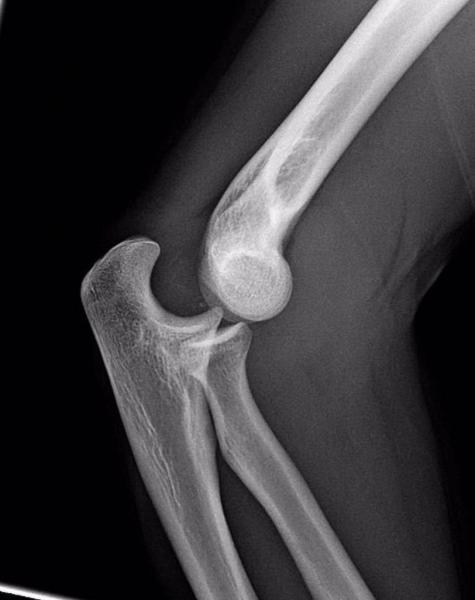

Desgast dels cartílags articulars